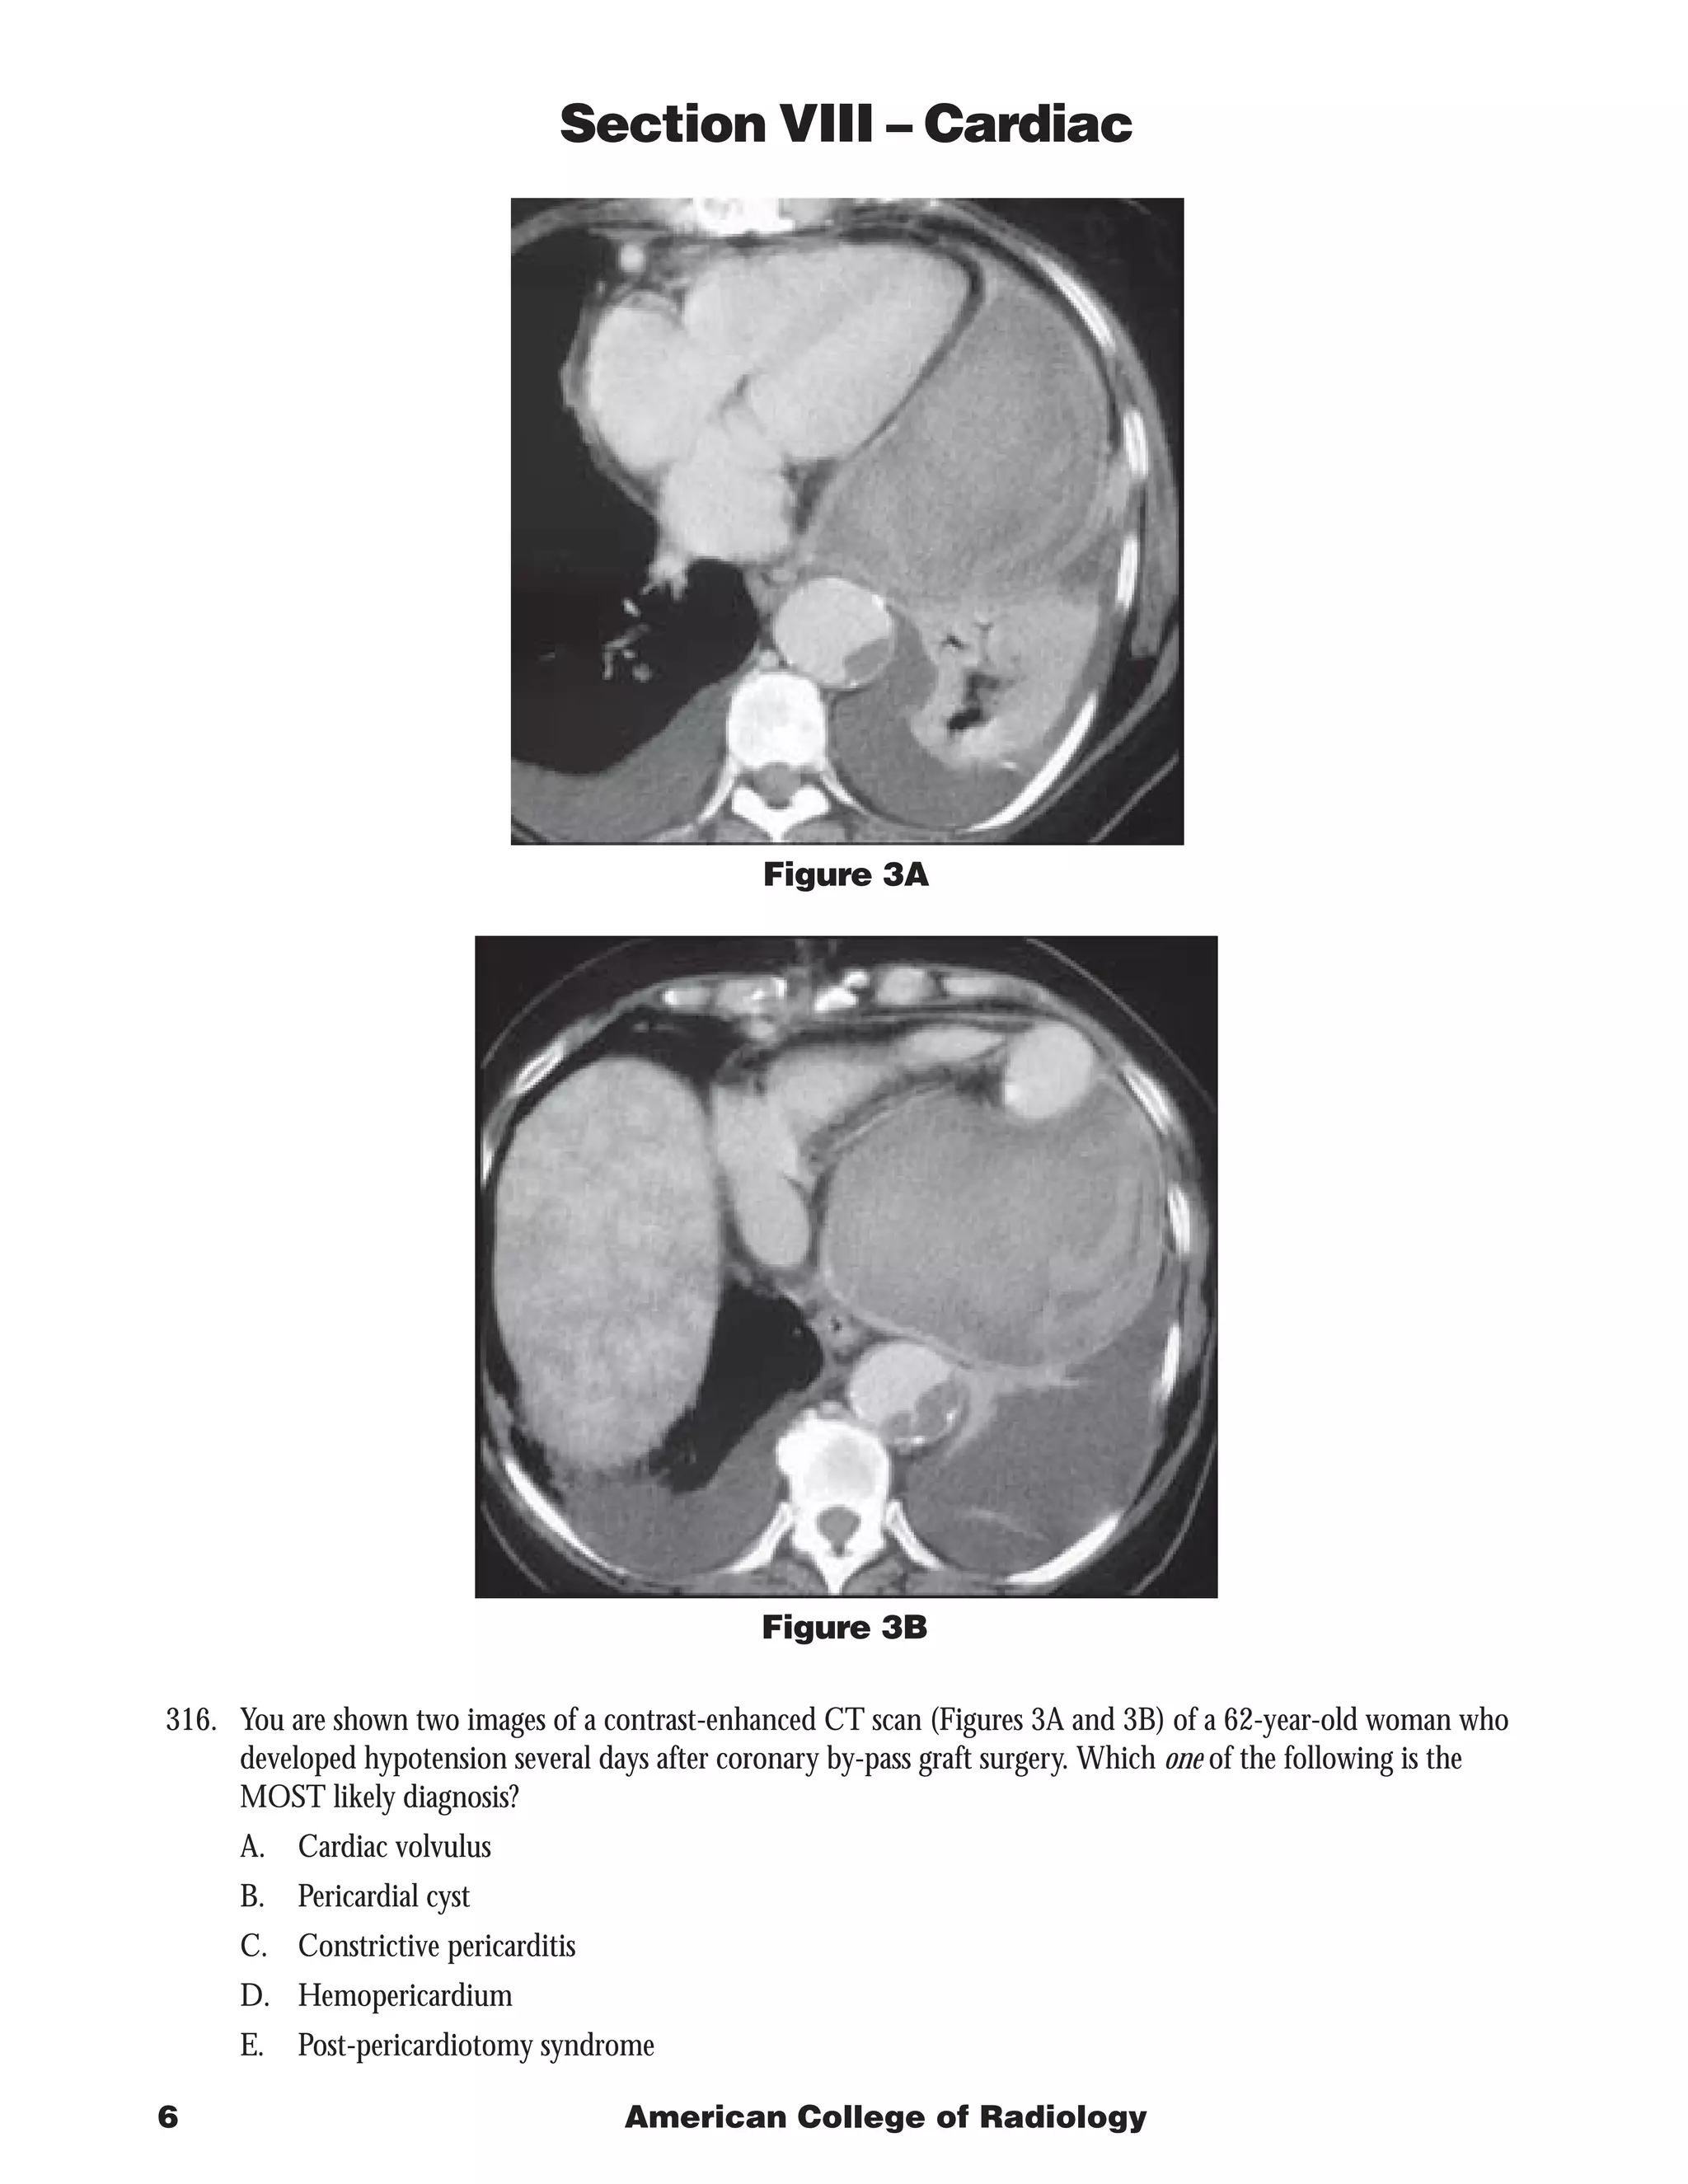

The CT images show a high-attenuation collection displacing the heart to the right, indicating hemopericardium or blood in the pericardial sac. Figure 3B further shows a brightly enhancing structure near a surgical clip on the distal posterior descending coronary artery, consistent with a pseudoaneurysm causing the hemorrhage. The findings are most consistent with hemopericardium developing several days after coronary bypass surgery.